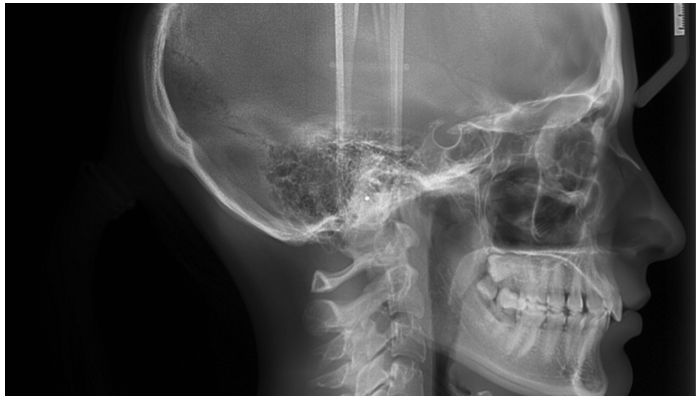

В боковой проекции

Этот специфический рентген является обязательным, когда планируется составление алгоритма ортодонтического лечения. Он изображает вид в профиль челюстей.

- Диагностика перед брекетами обязательно включает в себя боковой рентген. Эта форма служит для создания плана лечения. Дает возможность произвести ряд расчетов, вычислить необходимые углы и уточнить параметры, необходимые для процесса лечения. Рентгенологическое изображение определяет размеры челюстей, их соотношение и положение друг относительно друга. Все это позволяет врачу планировать крепление и возможность дальнейших действий в работе с коррекционными системами.